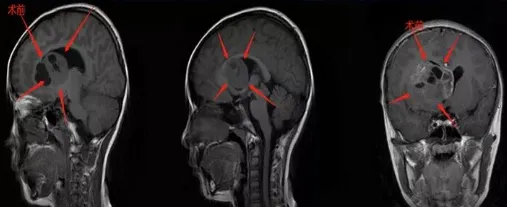

我知道女儿不会撒谎,于是连忙请假带她去了医院,结果却查出了一个巨大占位,肿瘤在基底节区,足足有50*41*37mm这么大,在核磁上看着特别吓人。

我看了教授既往的类似案例,也很快约了与教授的面诊,原本已经做好了一定的心理准备,没想到巴教授却说这是女儿的第一次手术,如果能达到高切除率,孩子术后的生存周期将显着延长,复发率也会大大降低,避免二次手术带来的伤害。而且他还可以在国内进行手术,争取实现最大范围切除。